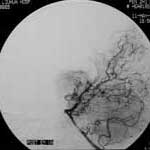

三、闭塞性脑血管病

----闭塞性脑血管病,如急性脑梗塞引起的偏瘫、颈动脉或椎基底动脉狭窄所致短暂性脑缺血发作(TIA)及可逆性神经 功能障碍(RIND),视网膜中央动脉或中央静脉闭塞引起的视力减退,静脉窦血栓性形成引起的颅内压增高等,均可通过 血管内的介入治疗得以改善,介入治疗的方法分溶栓、血管成形术或支架置入,根据病变选择不同的治疗方法。

2.急性梗塞动脉内接触性溶栓治疗的适应证:

(1)发病6小时内;

(2)CT或MEI检查没有梗塞及出血表现;

(3)对大脑中动脉卒中者,133XESPECT检查显示CBF残存超过每分钟15ml/100g;

(4)血管造影证实颅内血栓及部位;

(5)基底动脉溶栓可延至发病后48小时。